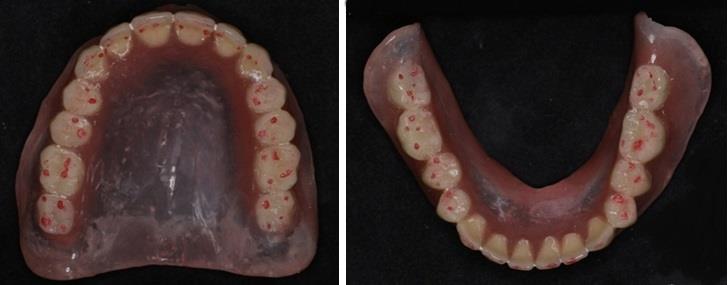

Полученная форма зубной дуги не соответствовала полу эллипсу, что вполне объяснимо индивидуальными особенностями челюсти. Нижняя дуга была близка к оптимальной форме (рис. 3).

Рис. 3. Форма искусственных зубных дуг на протезах